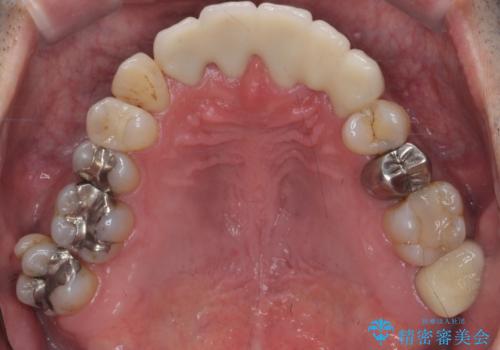

前歯の部分矯正を行い受け口を改善しました。

奥歯まで動かそうとすると顎の手術の適応になってしまうため、奥歯はそのままにして前歯のかみ合わせを改善しました。

また、奥歯はインプラント治療を行い、矯正で下の前歯を後ろに下げるのに使用しています。

時間はかかりましたがしっかり治療することができました。

右下のインプラント治療は横浜桜木町歯科院長大元先生にお願いしています。